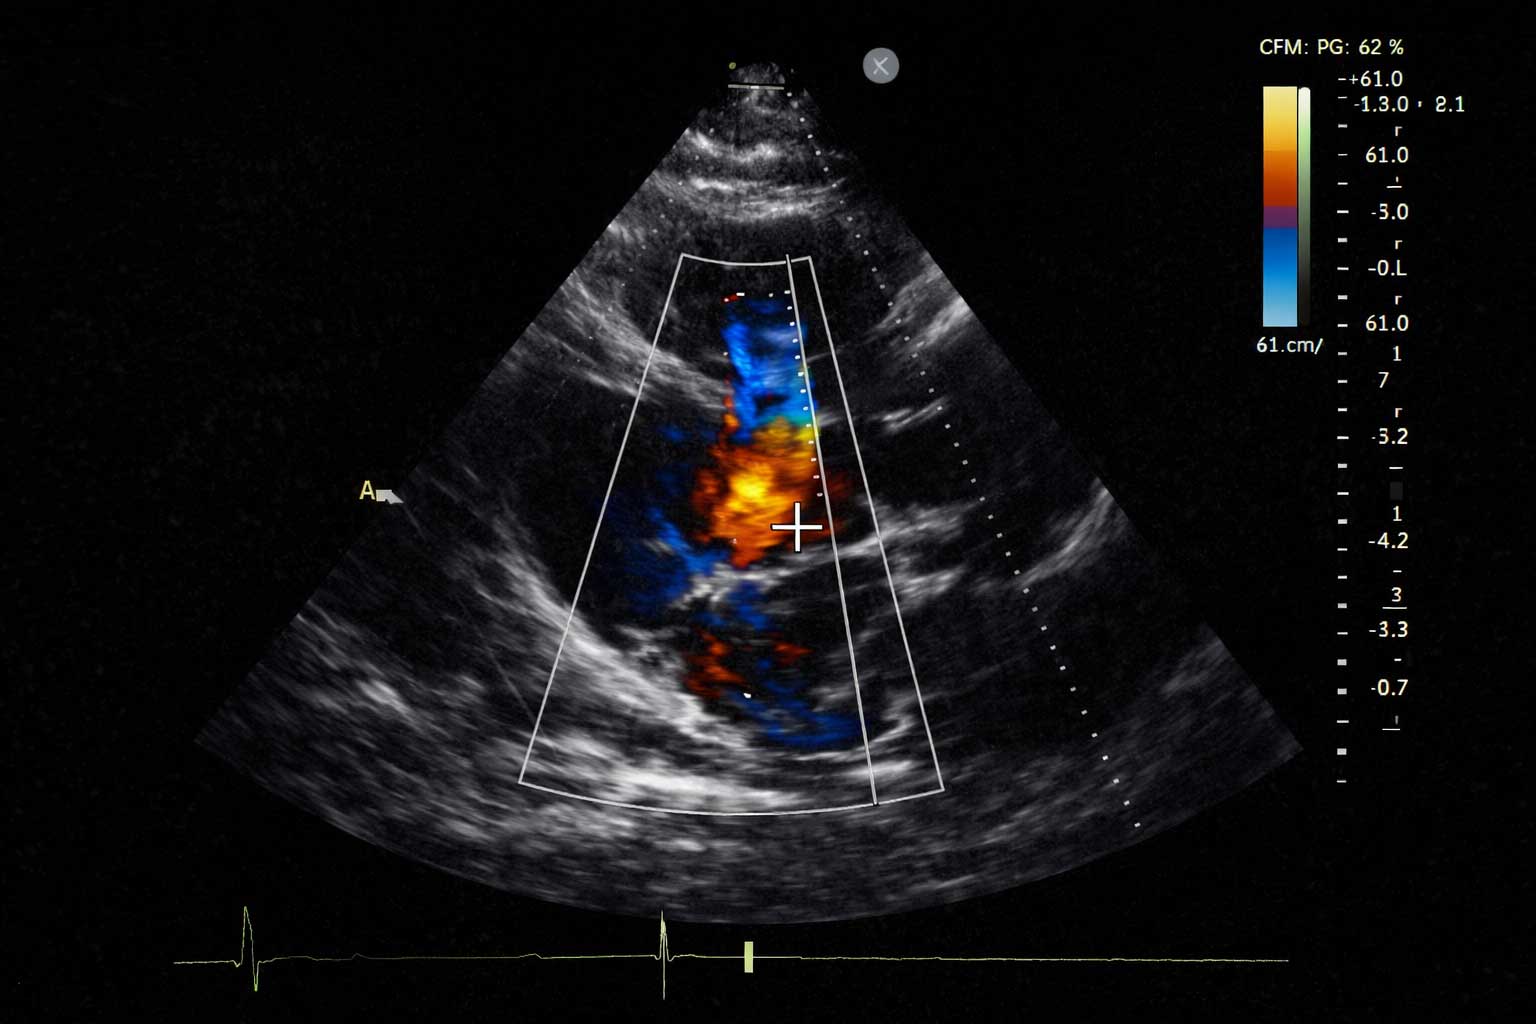

O ecocardiograma oferece uma avaliação detalhada e dinâmica do coração, permitindo analisar o funcionamento das câmaras, das válvulas e das estruturas cardíacas com alta precisão. É um exame essencial para identificar alterações precocemente e orientar um plano de cuidado personalizado.

Ecocardiograma